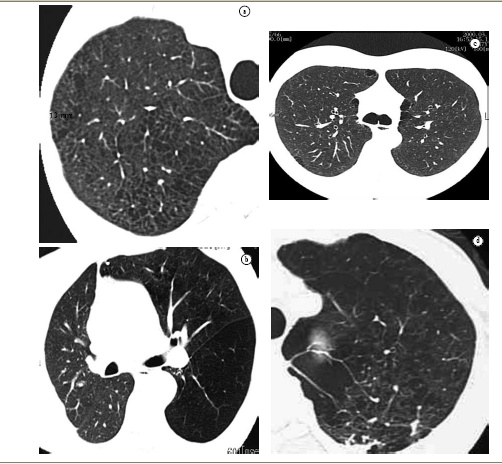

In contrast to conventional chestX-ray,computed tomography (CT) has proven very sensitive and specific in the evaluation of emphysema.(14,23-43)Since findings were first described in 1982,(14) CT has been used to detect, characterize and quantify the disease. Centrilobular emphysema is characterized by the presence of low attenuation areas, with ill-defined margins, generally without visible walls.(44) Lesions present a 'moth-eaten' appearance. When emphysematous lesions reach diameters greater than those of the lobes, part of their diameters can become well-defined, mimicking cysts, due to the presence of interstitial septa or major vessels surrounding the lesions. In a study that evaluated various signs of centrilobular emphysema, low attenuation areas in the medulla portion of the lungs, revealed on CT scans, correlated significantly with emphysema evaluated post mortem.(45) Other signs of emphysema include bullae (pseudocysts that contain air, with thin well-defined walls), rarefaction of vessels and distortion of the vasculature. Complementary signs of hyperinflation of the lungs that, when pronounced, are promptly identified on chest X-ray, might not be so obvious on CT. However, the anterior joint line of the lungs, measuring 3 cm in the anteroposterior portion, suggests hyperexpansion in the patient with emphysema.(46)

The high-resolution CT (HRCT) can differentiate among the various types of emphysema, in patients with mild or moderate disease,(47) depicting with great similarity the findings of pathological anatomy described above, according to which centrilobular emphysema presents: preference for upper thirds,(45) and it can be confined to these regions; low density multifocal areas resulting from the destruction of the alveoli, predominantly in the medullar portion, distant from the pleura(45); lesions that can be similar to small cystic air spaces, typically without an obvious wall; and lung surrounding lesions, which can be totally normal. With the progression of the disease, centrilobular emphysematous lesions become confluent.

HRCT, in panlobular emphysema, reveal a more uniform pulmonary destruction, with extensive low density areas, accompanied by vascular distortion and rarefaction. In classical panlobular emphysema, small focal low density areas, characteristic of centrilobular emphysema, are not found. In contrast to the latter, distribution is preferential in the lower thirds of the lungs.

Paraseptal emphysema is easily detected on HRCT scans, and presents as low density areas, with well-defined, hair-thin walls.(48) These pseudocysts are distributed in the subpleural regions or adjacent regions to larger bronchovascular cuffs. This emphysema pattern curiously have a 'saw-tooth' appearance and, occasionally, interstitial septa can seem particularly prominent; sometimes, they can mimic lymphangitic carcinomatosis at chest X-rays, which is promptly revealed on HRCT scans.(48)

Various studies have been dedicated to the evaluation of detection capacity, anatomopathological correlations and pulmonary function tests, as well as the quantification of the extent of the disease on CT scans.(23-48) It is the opinion of various authors that the quantification of emphysema by conventional X-ray is limited.(7,23,49) Therefore, CT has become the imaging method of choice for the quantification in vivo of this disease.

Some authors(39) studied quantification by visual score, with scale from 1 to 5, according to involvement of 0, 25, 50, 75% or 100% of the lungs. The correlation of this technique with pathological anatomy presents correlation of r = 0.91 in vitro (with cadaver pulmonary specimens). In vivo, this correlation is r = 0.81.(24-39) We should consider, however, that there are natural limitations when subjective analysis is used in the quantification of emphysema, whether the pathological anatomy analysis involves radiology, macroscopy or microscopy.

In an attempt to reduce the inherent subjectivity to the technique used by one author, other authors(31) proposed the visual stratification in classes, through overlapped grids on CT images, which presents good anatomopathological correlation. However, it is much too complicated and quite subjective. The level and opening of the window in Hounsfield units (HU) selected for CT imaging analysis can influence significantly in the identification of emphysema areas.(29-34) The best window selection for the visual identification of emphysema is the one using opening including 1100 HU, with level or fixed center at −750 HU. Another limitation common to the two techniques is the lack of consensus on the minimum number of necessary tomographic slices for a representative quantification of the whole of the lungs. In addition to these problems, it is reported that the tube current also influences significantly in the visual subjective identification of emphysema on HRCT scans.(39)

Predictably, the comparison between quantification methods by visual scores and those performed automatically by graphic computing demonstrated significant difference in favor of automation.(27) One study(50) demonstrated that regardless of the experience of the observer, there is a tendency to overestimate emphysema at visual analysis, and that densitometry correlates better with morphometric data.

In this evolution toward automation, it is not possible to overlook the important step represented by the research conducted in another study,(28) in which it was demonstrated that patients with emphysema present more areas with density from −900 HU to −1000 HU than do those without emphysema. Later, other studies confirmed the proposal that CT can objectively discriminate patients with and without emphysema.(37,41) These techniques were studied in detail by one author who demonstrated the advantages of the use of density masks, which present correlation r = 0.89 with pathological anatomy.(43) The density mask is one of the most important techniques in the semi-automatic evaluation of emphysema. Other authors(21) studied the use of the technique of projections of minimum intensities, which subtracts all high density structures from the image, highlighting the areas of emphysema. The studies of some authors(34) represented a new milestone in the investigation of this disease, establishing the threshold value of −950 HU as adequate to set apart lung with normal density and lung with density too close to air or with emphysema. This threshold has, since then, been one of the most frequently used in the quantification of emphysema by CT.